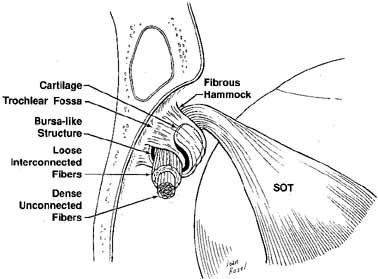

and superior oblique tendon averages 4.7 mm.29 The superior oblique muscle depresses, intorts, and abducts the eye (see Fig. 11). The trochlea is situated in a shallow fossa bearing its name on the anteromedial

orbital roof. Crescent-shaped cartilage is suspended

from the periorbita on either end by the fibrous pillars. The central

fibers of the reflected tendon exhibit few adhesions to the neighboring

fibers, whereas those peripheral in the tendon are connected in a loose

fashion to the fibers of the tendon. Located between the cartilage

and the tendon is a bursalike structure, presumably to reduce friction.30 The cartilage is a U-shaped ring with a grooved flange that supports

the reflected tendon posteriorly and laterally from the front of

the trochlea (Fig. 16).31 The periorbita to which the trochlea is attached can be carefully elevated

from the bone by the surgeon and replaced, if needed, although injury

to the tissues surrounding the trochlea can cause scarring and possible

superior oblique restriction or Brown's syndrome.  Fig. 16 Schematic drawing of the right trochlea. Tendon is supported by a layer

of cartilage suspended by fibrous supports from the periorbita. Central

fibers of the tendon are strong with dense unconnected fibers. Peripheral

tendon shows loose interconnected fibers. (SOT, superior oblique tendon) (Adapted from Helveston EM, et al: The trochlea: A study of the anatomy

and physiology. Ophthalmology 1982:89:124) Fig. 16 Schematic drawing of the right trochlea. Tendon is supported by a layer

of cartilage suspended by fibrous supports from the periorbita. Central

fibers of the tendon are strong with dense unconnected fibers. Peripheral

tendon shows loose interconnected fibers. (SOT, superior oblique tendon) (Adapted from Helveston EM, et al: The trochlea: A study of the anatomy

and physiology. Ophthalmology 1982:89:124)